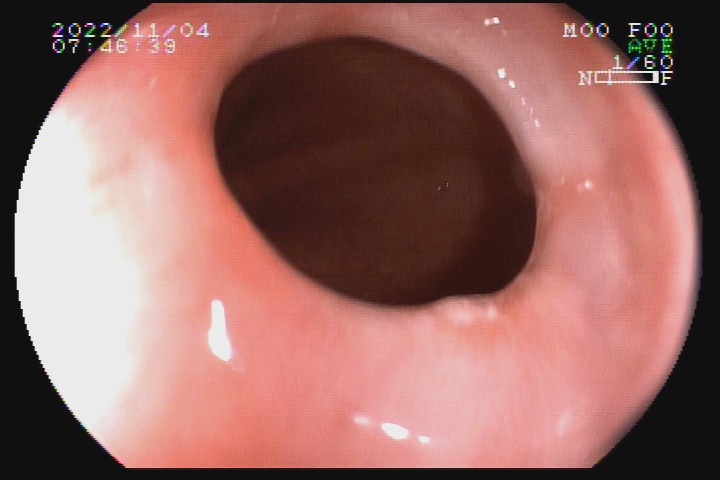

Ao refluxo ácido persistente é atribuída uma das causas de formação de anel em esfíncter esofágico inferior, conhecido como anel de Schatzki, que poderá se manifestar na forma de disfagia, sendo tratada com dilatação mecânica com balão hidrostático.